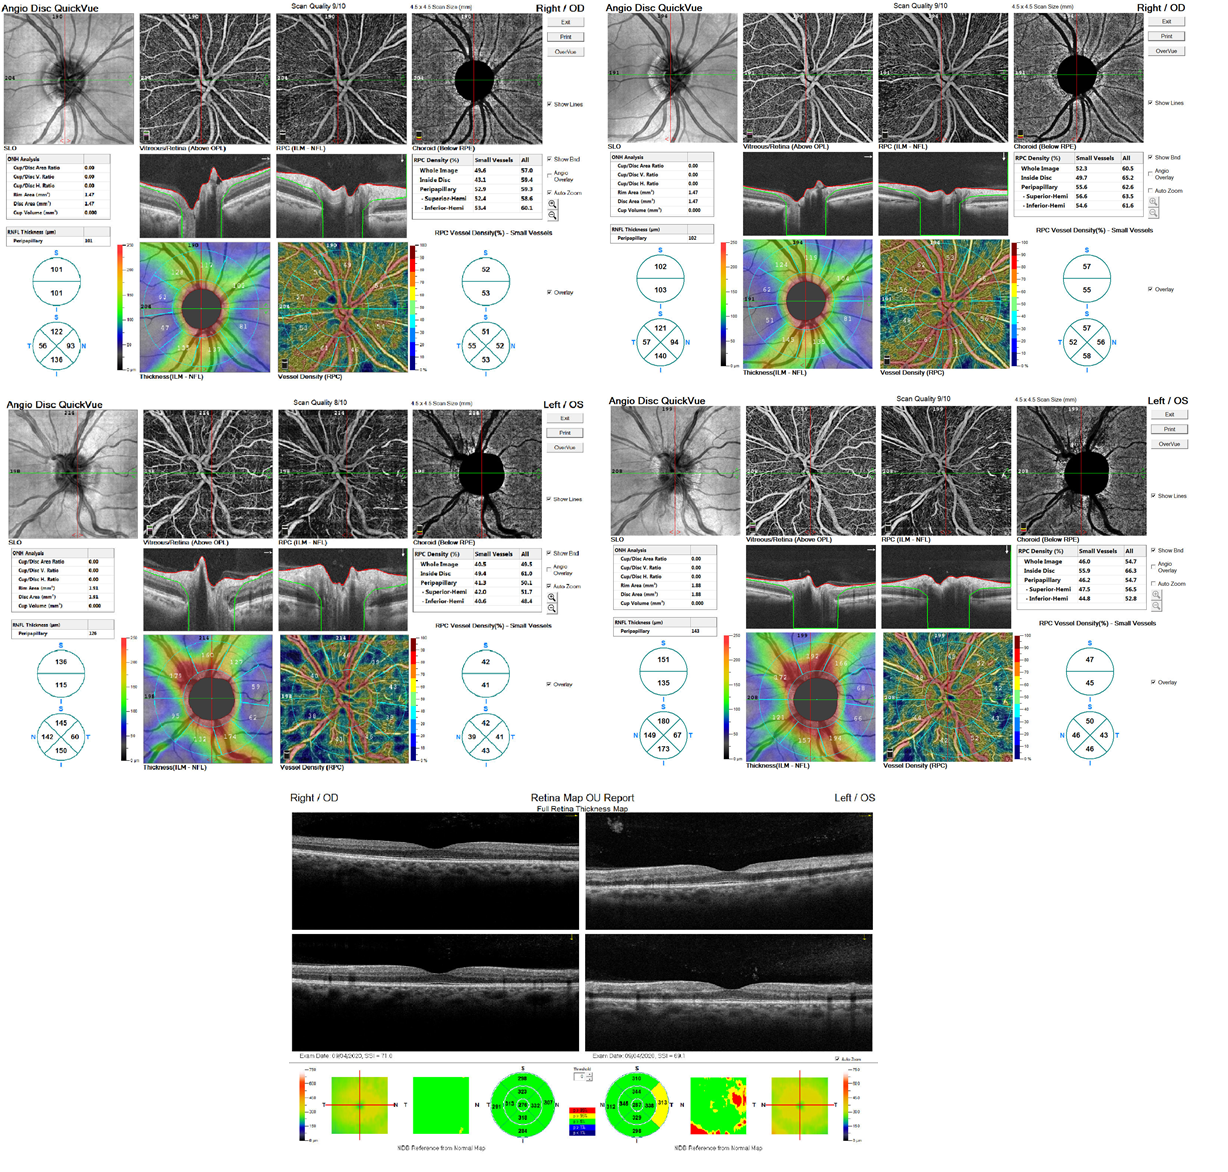

Fundus photography confirmed the macular findings, and AF showed hypoautofluorescent lesions over the optic nerve and macula (Figure 1). Computerized perimetry revealed a non-specific defect in OD and a centrocecal defect in OS (Figure 2). OCT of the optic nerve showed mild superior elevation in OS with RNFL analysis (Figure 3), and marked vascular density reduction in 360° in the optic nerve of OS (Figure 4). Macular OCT revealed an alteration in the external plexiform layer of OS with abundant temporal hyperreflective lesions, and a preserved foveal architecture in both eyes (Figure 5). OCTA of the macula showed a decrease in vascular density in the deep superior and choriocapillaris layers (Figure 6). Based on these findings, aspirin was reintroduced, and a follow-up was scheduled in 4 weeks with computerized perimetry, OCT, and OCTA, with a presumptive diagnosis of NAION and PAMM.

Figure 3 OCT of the optic nerve showed mild superior elevation in OS with RNFL analysis.

Figure 4 Marked vascular density reduction in 360° in the optic nerve of OS.

At the follow-up, the patient reported that despite persistent visual symptoms, these did not significantly affect his visual field. Ophthalmic exams showed improvement in the visual field, with a more limited paracentral scotoma (Figure 7). Macular OCT showed fewer hyperreflective lesions in the temporal external plexiform layer, but worsening RNFL analysis due to increased optic nerve edema in OS secondary to NAION (Figure 8). OCTA indicated improved vascular perfusion in all retinal layers (Figure 9).

Figure 8 RNFL analysis due to increased optic nerve edema in OS secondary to NAION.

Figure 9 OCTA indicated improved vascular perfusion in all retinal layers.